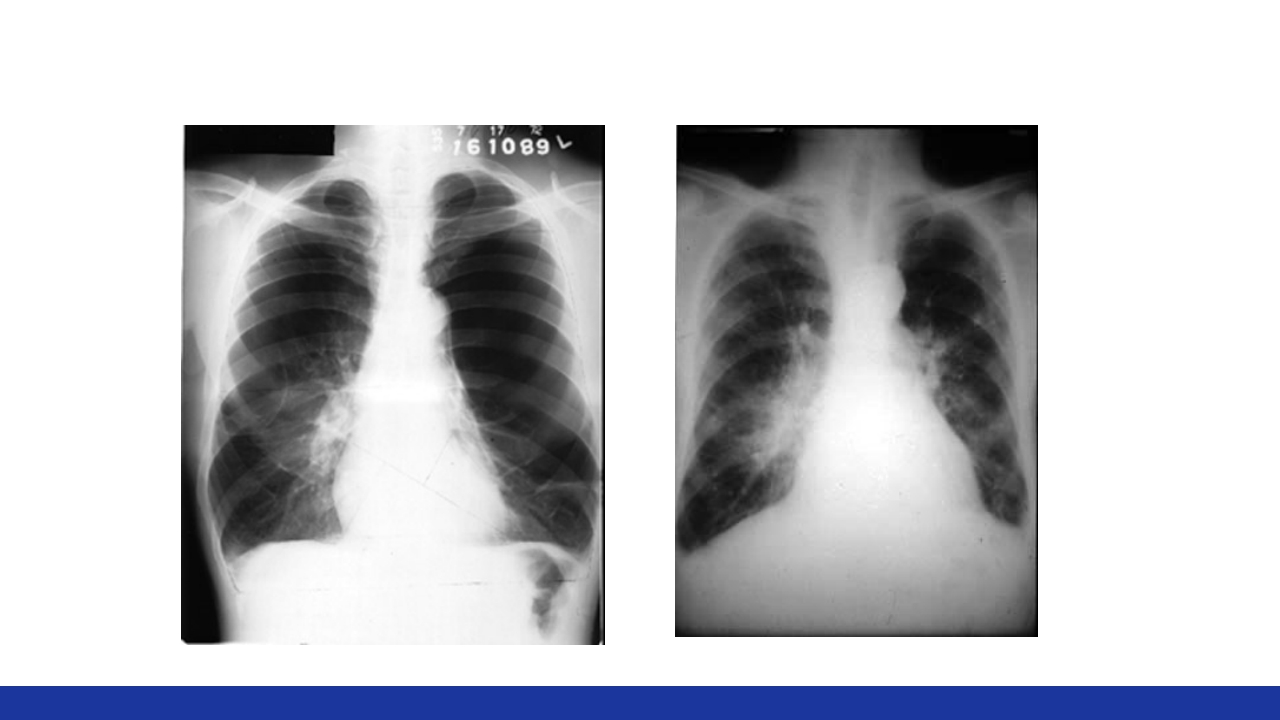

慢性肺源性心脏病 Chronic Pulmonary Heart Disease 主讲人:XXX 教学目标 【掌握】 1.慢性肺源性心脏病病人的护理护理评估。 2.慢性肺源性心脏病病人的临床表现与并发症。 3.慢性肺源性心脏病病人的护理措施。 【熟悉】 慢性肺源性心脏病的主要护理诊断及治疗要点; 【了解】 慢性肺源性心脏病的病因及发病机理。 案例 男性,63岁。慢性咳嗽、咳痰20余年,逐渐加重的呼吸困难5年。有吸 烟史40年左右。T 36.2℃,BP 130/80mmHg,神志清,胸廓呈桶状,双 肺叩诊过清音,触觉语颤减弱,肺泡呼吸音减弱,肺动脉瓣区第2心音 亢进,三尖瓣区可闻及收缩期杂音。血白细胞10×109/L,中性粒细胞 70%。X线胸片:双肺透亮度增高,肺动脉扩张。 问题:①临床诊断? ②主要护理问题? ③健康指导? 定义...